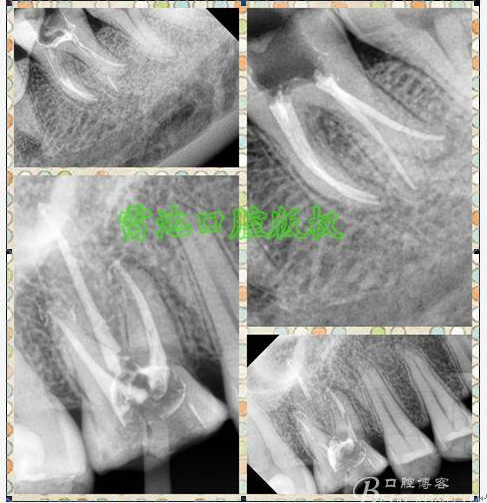

E 、X線影像學(xué)的檢查研判能力: 這點(diǎn)不需要強(qiáng)調(diào)太多,對(duì)于普通的非CBCT的二維影像對(duì)醫(yī)生讀片能力有一定的要求,有個(gè)逐步提高的過(guò)程,非一蹴而就,需要學(xué)會(huì)把二維的X線影像與三維的解剖結(jié)構(gòu)進(jìn)行良好的對(duì)應(yīng)結(jié)合,對(duì)于某些鈣化的髓室底,應(yīng)通過(guò)想象把根管口的分布、根管的走向以及各種變化通過(guò)想象投射到對(duì)應(yīng)的髓室底上;

1、查閱各種文獻(xiàn),MB2的發(fā)生率在52-96%之間,治療時(shí)遺漏是上頜磨牙根管治療失敗的主因,2、一般位于MB1根管口與腭根管口方向的0.5-5mm范圍內(nèi),而大多數(shù)都位于MB舌側(cè)的1-3mm處,其中2mm以內(nèi)占85.7%,3、MB1-P根管口連線與MB1-MB2根管口的連線夾角大部分(74.3%)在30度以內(nèi);4、MB2的尋找大部分需要去除相應(yīng)部位的牙本質(zhì);5、當(dāng)找到的MB根管口呈“長(zhǎng)線型”且有深色凹線向舌側(cè),或者找到的MB根管口明顯偏頰多提示有MB2的可能;6、DOM(牙科手術(shù)顯微鏡)的使用有助于找尋MB2;